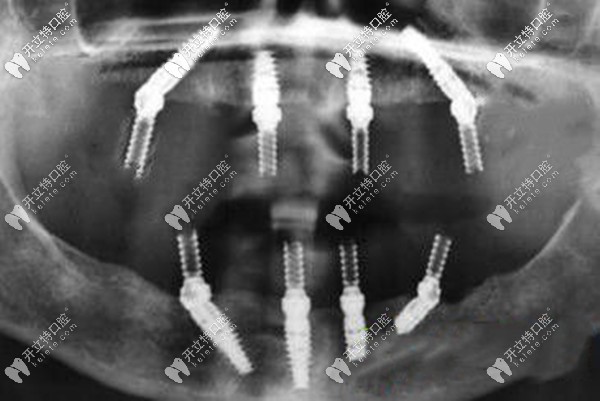

如果,牙槽骨量不足,做ALL-ON-4全口即刻負(fù)重種植牙,不用植骨,上下頜各植入4顆種植體就能恢復(fù)全口的咀嚼功能,而且是當(dāng)天種牙當(dāng)天就能吃東西。

一般做all-on-4種植牙需要導(dǎo)板,而適合的種植體只有韓系和瑞典諾貝爾,年齡較大的可以選擇性價比高的韓系植體,半口的價格大概7萬起、全口13萬起;年輕或不差錢的就用瑞典諾貝爾種植體,半口16萬起、全口28萬起。